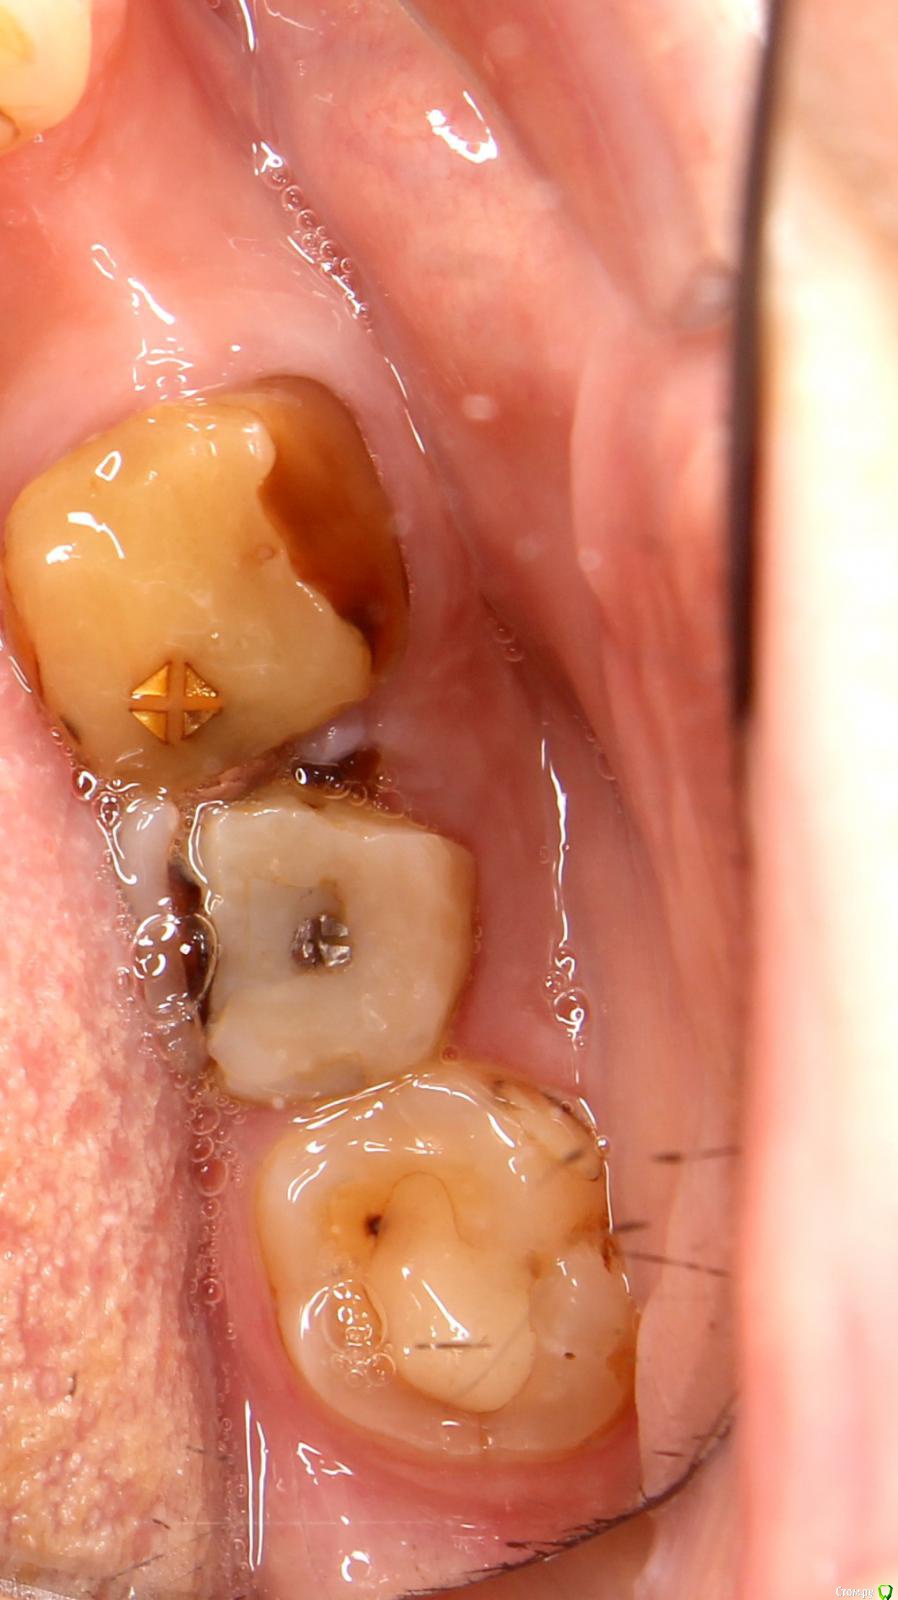

LOLga777 Опубликовано 24 ноября, 2019 Поделиться Опубликовано 24 ноября, 2019 (изменено) Здравствуйте, уважаемые врачи.37-й зуб. Депульпирован, стояла большая пломба. В 2013 году откололась наружная стенка зуба, скол близко к корню. Стоматологом № 1 был поставлен штифт, коронка восстановлена пломбой (фото с торчащим штифтом от 2013 года). Через год наружная часть пломбы откололась прямо по штифту, так ходила три года, ничего не царапало, не мешало. В 2016 году стоматолог № 2 в поликлинике уговорила запломбировать, в результате сделала скошенную наружную часть пломбы. Фото ротовой полости справа от 07.2019 г. прилагаю. Вопрос: что делать с 37-й зубом? Хирург не хочет удалять, говорит, что можно восстановить пломбой, и боится повредить 36-й. Не знаю, видно ли на снимках, в каком канале стоит штифт и можно ли поставить еще один штифт (второй штифт врач не поставила, насколько я помню, из-за того, что будет дороже и еще что-то там может не выдержать). Без второго штифта пломба, повторяющая анатомическую форму зуба, я считаю, простоит максимум год. С 36-м зубом тоже непонятно что делать, не идет ли там процесс кариеса на корне… Между корнями что-то черное (на КТ и 2016 года и 05.2019 года). Не хотелось бы покрывать коронкой зуб с гранулемой между корнями. Стоматолог предложил рассверлить пломбу и посмотреть.У меня ВОПРОС: можно ли будет что-то увидеть после рассверливания зуба, если процесс идет под «дном»? После сверления снимется еще часть тканей, а их там и так мало. По вкладкам и коронкам на 37-й зуб, наверное, надо продублировать тему в раздел «Протезирование». P.s. Есть большое количество других проблем Изменено 24 ноября, 2019 пользователем LOLga777 Ссылка на комментарий